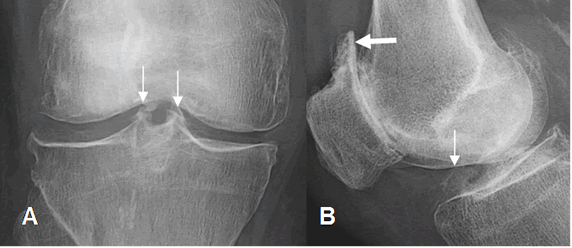

Fig 201. Osteofitos centrales.

A: Rx AP y B: Rx lateral de rodilla. Formación de osteofitos centrales (Flecha delgada). En B existen cambios degenerativos en la articulación patelofemoral, con pérdida del espacio, esclerosis y osteofitos. (Flecha gruesa).